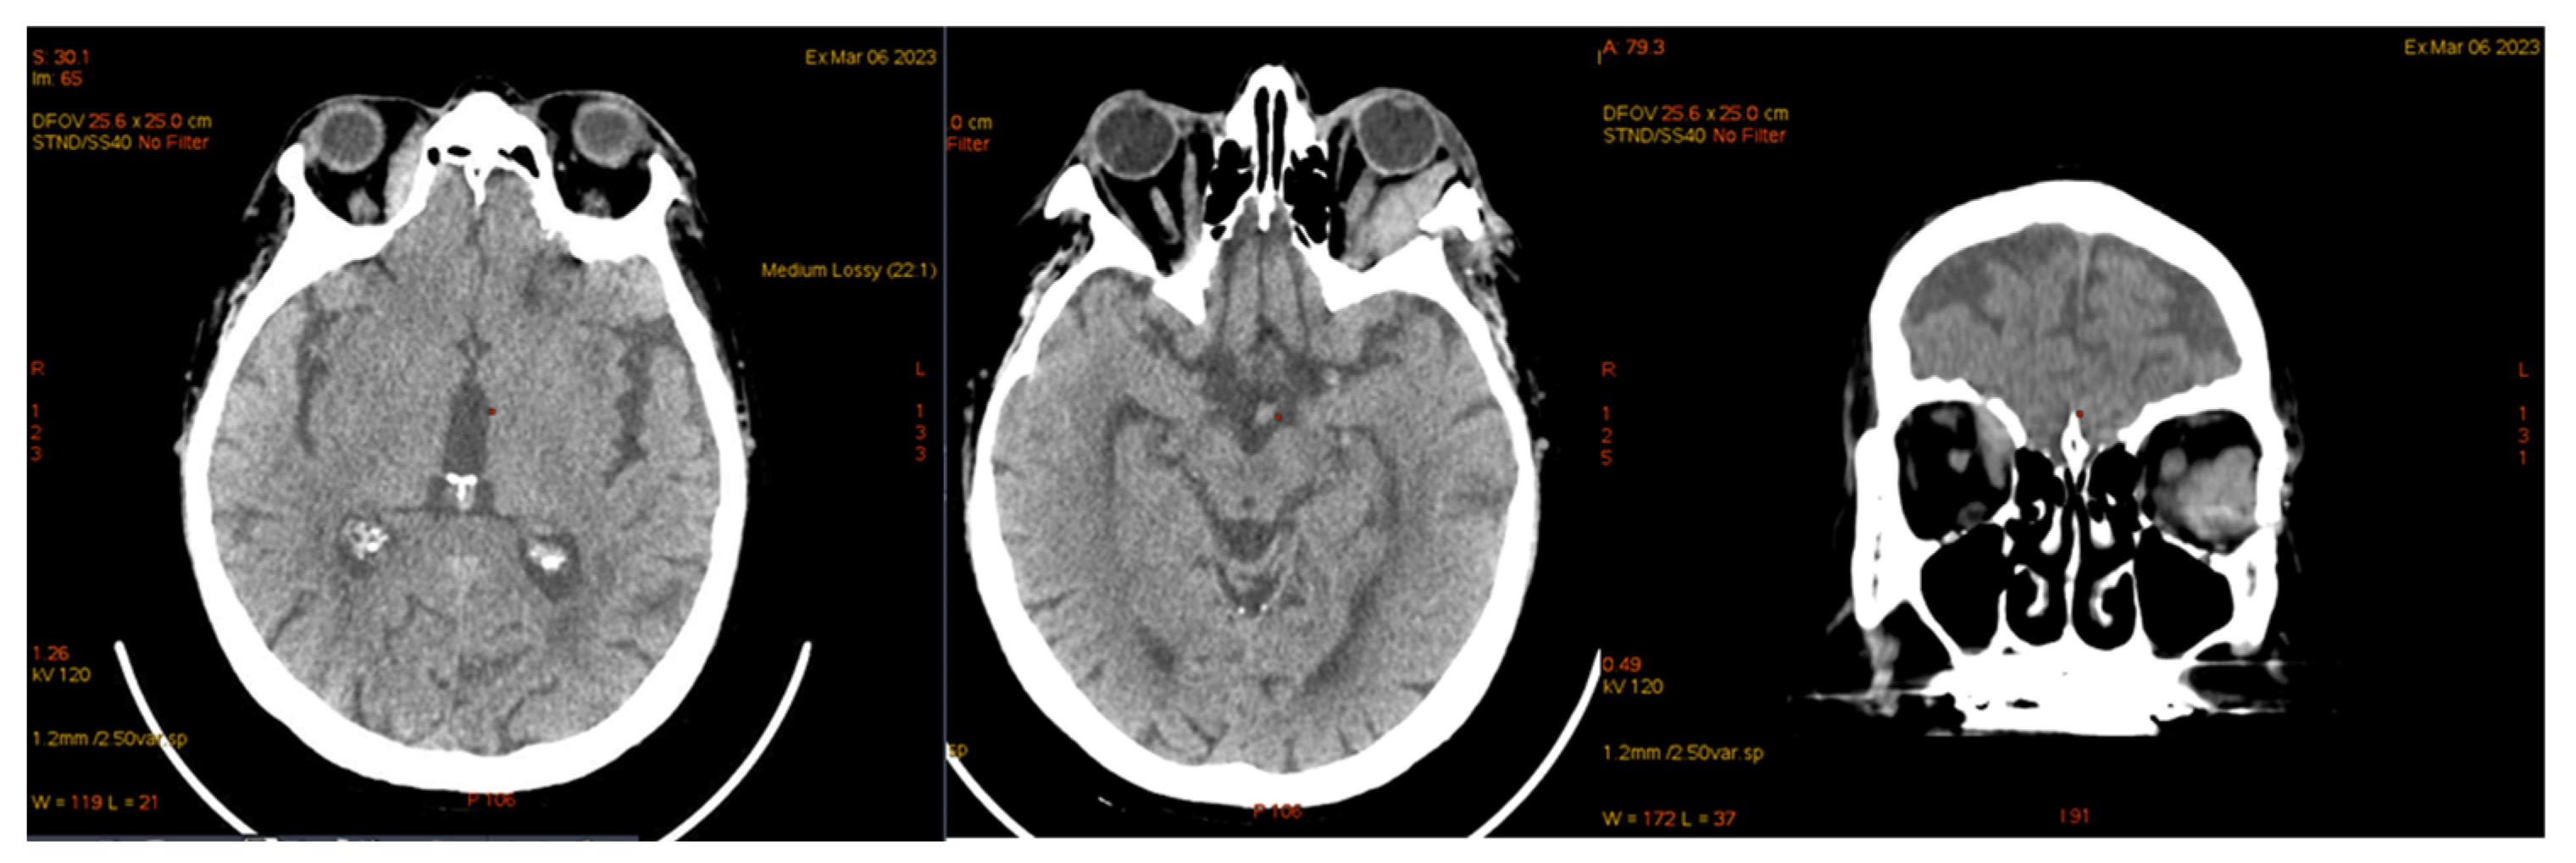

| January 2023 | second extramedullary relapse bilateral ocular left eye clinically, imaging, and biopsy demonstrated right eye demonstrated by imaging | methotrexate, asparaginase, calcium folinate radiotherapy, 30 gy/15 sessions result: imaging complete remission |